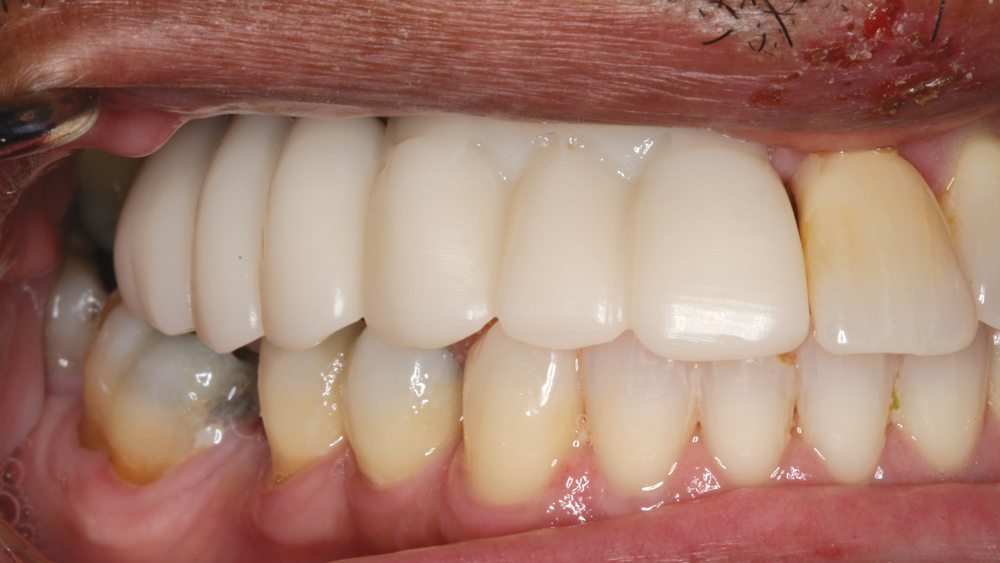

The chief complaint from my patient, Weldon, was missing teeth and gaps between his teeth. The preoperative evaluation showed periodontally involved and non-restorable maxillary right teeth #2–8 and significant periodontal bone loss, which would need to be addressed. The periodontal condition was stable in the patient’s left maxilla, and he was satisfied with the existing esthetics in that quadrant.

Weldon desired “permanent teeth” and rejected the option of a removable appliance, as he was dissatisfied with the partial he had been wearing prior to treatment. As a 70-year-old with controlled hypertension, no other significant medical considerations, and relatively healthy, functional and esthetic maxillary left teeth, he elected to restore the maxillary right quadrant with a fixed, implant-supported prosthesis. BruxZir® Solid Zirconia is my material of choice for this type of restoration because of its strength and esthetics. Further, the material can be milled as a monolithic implant bridge, with lifelike pink stain applied to the gingival areas, to predictably and fully restore form and function for the patient, even in edentulous spans where significant tissue loss has occurred.

RESTORATIVE TECHNIQUES FOR ESTHETICS AND OCCLUSION

Esthetics and occlusion can be challenging in these types of cases. Restoring half an arch and trying to mirror the contralateral soft tissue and dentition with proper contours and shade requires patience and resolve. The lab provided a PMMA try-in prosthesis, which I evaluated with Weldon. The try-in allowed us to easily resolve any discrepancies with the prosthetic design and develop ideal occlusion. Once Weldon agreed on the esthetics, the PMMA provisional was returned to the lab and duplicated in BruxZir Solid Zirconia. This extra step eliminates excessive chairside adjustments upon seating of the final prosthesis.

The PMMA try-in prosthesis ... allowed any necessary adjustments to easily be made to the prosthetic design prior to milling the final BruxZir restoration.

BruxZir Solid Zirconia has proven to be extremely strong yet compatible with opposing natural dentition; the material exhibits minimal wear on the opposing enamel. Its color and shading are extremely natural in appearance, and I have no concerns about chipping or cracking of the material over time. The final seating of the prosthesis was straightforward, and I have confidence that the material is a long-lasting solution. Weldon was thrilled with the final restoration, as we were able to surpass his expectations and provide him with a fixed, functional, esthetic result.

Understanding the foundation required to predictably place dental implants, including effective extraction techniques, socket management and grafting procedures, has improved the prognosis. Working with talented and well-trained laboratory technicians helps us plan the final prosthetic result prior to any surgical procedure. Innovative laboratory techniques and materials provide outstanding functional and esthetic results. As for Weldon, his BruxZir implant bridge ensures an excellent long-term prognosis as well as restored esthetics in an area that was compromised by tissue loss prior to treatment.